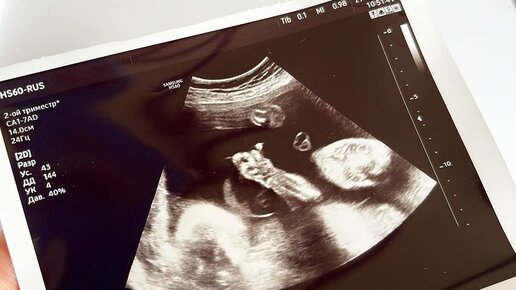

Тимофей. Когда мальчик родился, его маму спросили: «Вы же заберёте ребёнка?» История одной московской семьи